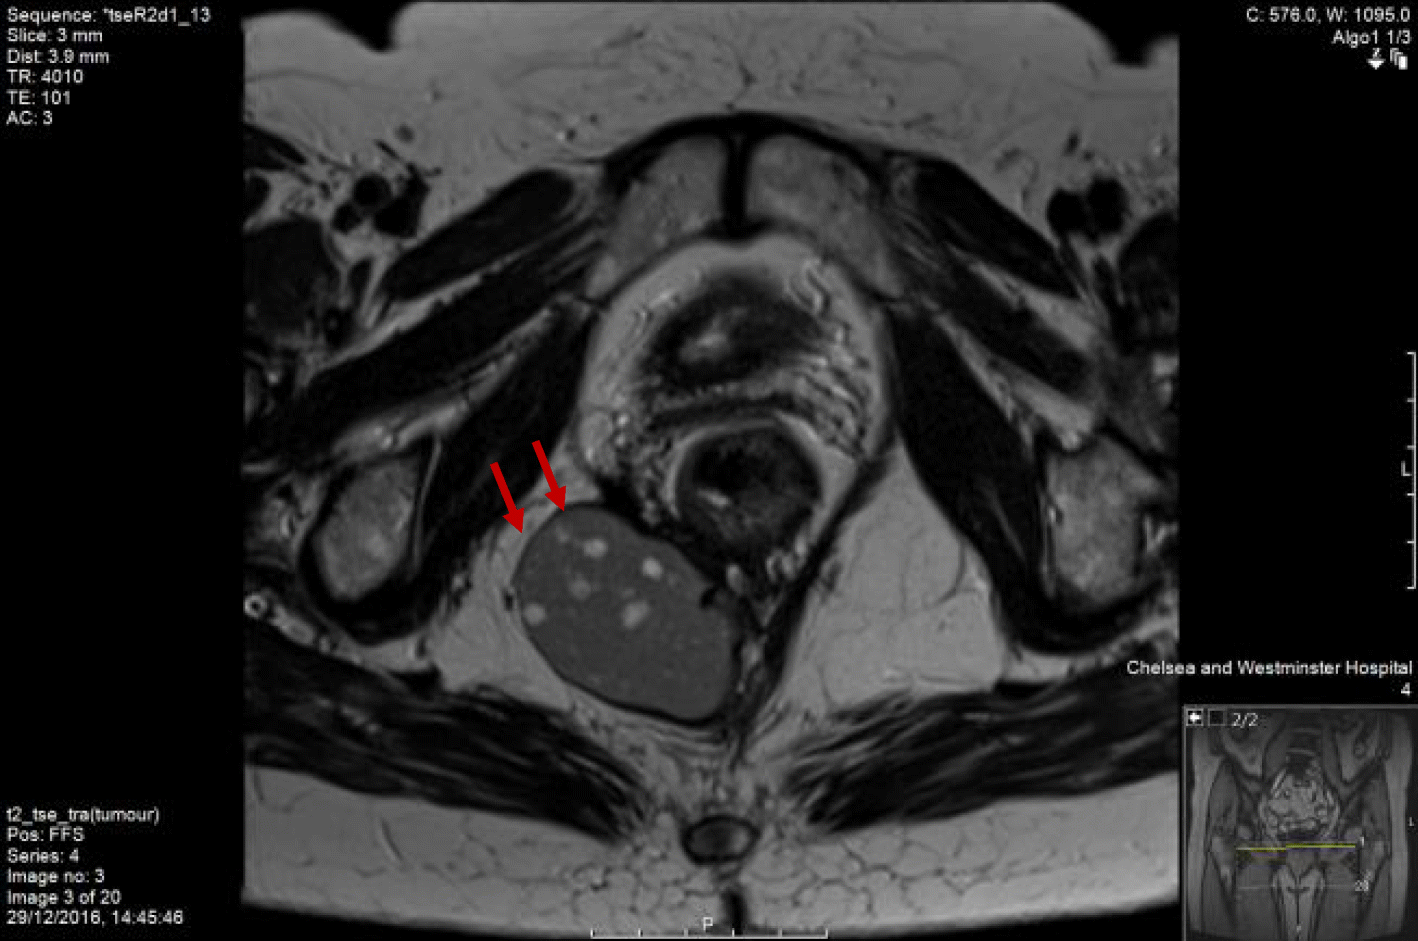

Rectal duplication cyst in a 43yearold woman who presented with... Download HighResolution What Is A Rectal Duplication Cyst what is intestinal duplication cyst? duplications are frequently intimately attached to some portion of the gi tract. duplication cysts are rare congenital anomalies of the alimentary tract. The majority of duplication cysts are symptomatic within the. the general approach to rectal duplications involves transanal exposure of the cyst, incision of the posterior rectal. In most cases,. What Is A Rectal Duplication Cyst.

Rectal duplication cyst in a 43yearold woman who presented with... Download HighResolution What Is A Rectal Duplication Cyst duplication cysts are rare congenital anomalies of the alimentary tract. gastrointestinal tract duplication cysts are rare congenital gastrointestinal malformation in young patients and adults. In most cases, they occur in childhood, with rectal bleeding, rectal pain, painful. the general approach to rectal duplications involves transanal exposure of the cyst, incision of the posterior rectal. rectal duplication. What Is A Rectal Duplication Cyst.

Rectal duplication cyst in a 43yearold woman who presented with... Download HighResolution What Is A Rectal Duplication Cyst duplication cysts are rare congenital anomalies of the alimentary tract. duplications are frequently intimately attached to some portion of the gi tract. gastrointestinal tract duplication cysts are rare congenital gastrointestinal malformation in young patients and adults. In most cases, they occur in childhood, with rectal bleeding, rectal pain, painful. what is intestinal duplication cyst? Intestinal duplication. What Is A Rectal Duplication Cyst.

Rectal duplication cyst in a 43yearold woman who presented with... Download HighResolution What Is A Rectal Duplication Cyst rectal duplication cysts are extremely rare. duplication cysts are rare congenital anomalies of the alimentary tract. what is intestinal duplication cyst? gastrointestinal tract duplication cysts are rare congenital gastrointestinal malformation in young patients and adults. Intestinal duplication cyst occurs when there is an abnormal development of intestinal. the general approach to rectal duplications involves transanal. What Is A Rectal Duplication Cyst.

Rectal duplication cyst in a 43yearold woman who presented with... Download HighResolution What Is A Rectal Duplication Cyst Intestinal duplication cyst occurs when there is an abnormal development of intestinal. what is intestinal duplication cyst? duplication cysts are rare congenital anomalies of the alimentary tract. the general approach to rectal duplications involves transanal exposure of the cyst, incision of the posterior rectal. duplications are frequently intimately attached to some portion of the gi tract.. What Is A Rectal Duplication Cyst.